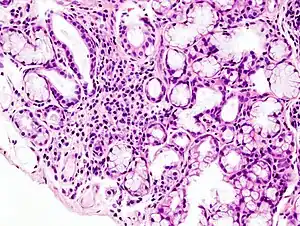

Image with a microscope of focal lymphoid infiltration in the minor salivary gland associated with Sjögren's syndrome.

While the exact cause is unclear, it is believed to involve a combination of genetics and an environmental trigger such as exposure to a virus or bacterium.[4] It can occur independently of other health problems (primary Sjögren's syndrome) or as a result of another connective tissue disorder (secondary Sjögren's syndrome).[3] Sjögren's syndrome may be associated with other autoimmune diseases, including rheumatoid arthritis (RA), systemic lupus erythematosus (SLE) or systemic sclerosis. The inflammation that results progressively damages the glands.[7] Diagnosis is by biopsy of moisture-producing glands and blood tests for specific antibodies.[2] On biopsy there are typically lymphocytes within the glands.[2]

A lip/salivary gland biopsy takes a tissue sample that can reveal lymphocytes clustered around salivary glands, and damage to these glands from inflammation. This test involves removing a sample of tissue from a person's inner lip/salivary gland and examining it under a microscope. On such biopsies, the single most important test result in the diagnosis of the oral component of Sjögren syndrome is likely the focus score, which is the number of mononuclear cell infiltrates containing at least 50 inflammatory cells in a 4 mm2 glandular section.[53] The Chisholm-Mason grades are also widely used for salivary gland biopsies (see table).[54]